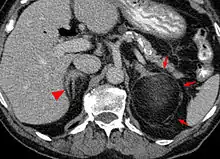

الورم الشحمي النقوي (بالإنجليزية: Myelolipoma) هو ورم حميد يتكون من نسيج دهني والخلايا المكوِّنة للدم بنسب مختلفة.[1] قد يظهر في الغدة الكظرية[2] أو خارجها.[3]

الورم الشحمي النقوي نادر جدًّا، يعثر عليه بشكل غير متوقع خلال التشريح الجنائي في 0.08% إلى 0.4% من الحالات. ينشأ عادة في الغدة الكظرية، لكنه لا يمثل أكثر من 3% من أورام الكظر. وقد يتكون في مناطق أخرى من الجسم كالمنصف والكبد والقناة الهضمية.[1]

في الغالب لا يظهر الورم من خلال الأشعة المقطعية أو أشعة الرنين المغناطيسي، وقد يظهر عن طريق التصوير الشعاعي بالأشعة السينية.